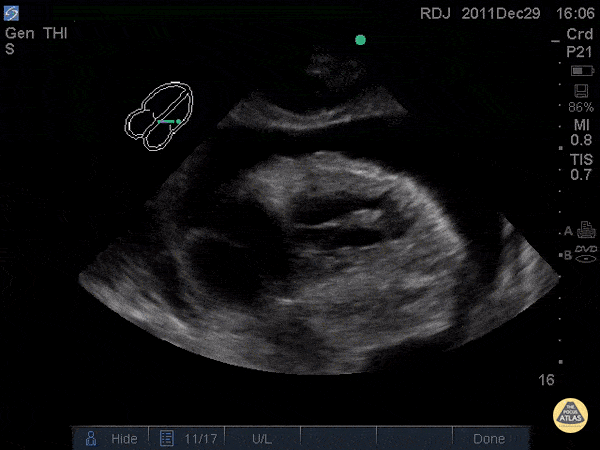

Pericardial Disease - Chronic Pericardial Effusion

WCUME17 submission for "Creative Caption" "When the turtle's head appears you know you're in trouble!" Patient with chronic pericardial effusion and... a heart that looks like a snapping turtle? Dr. Robert Jarman - UK